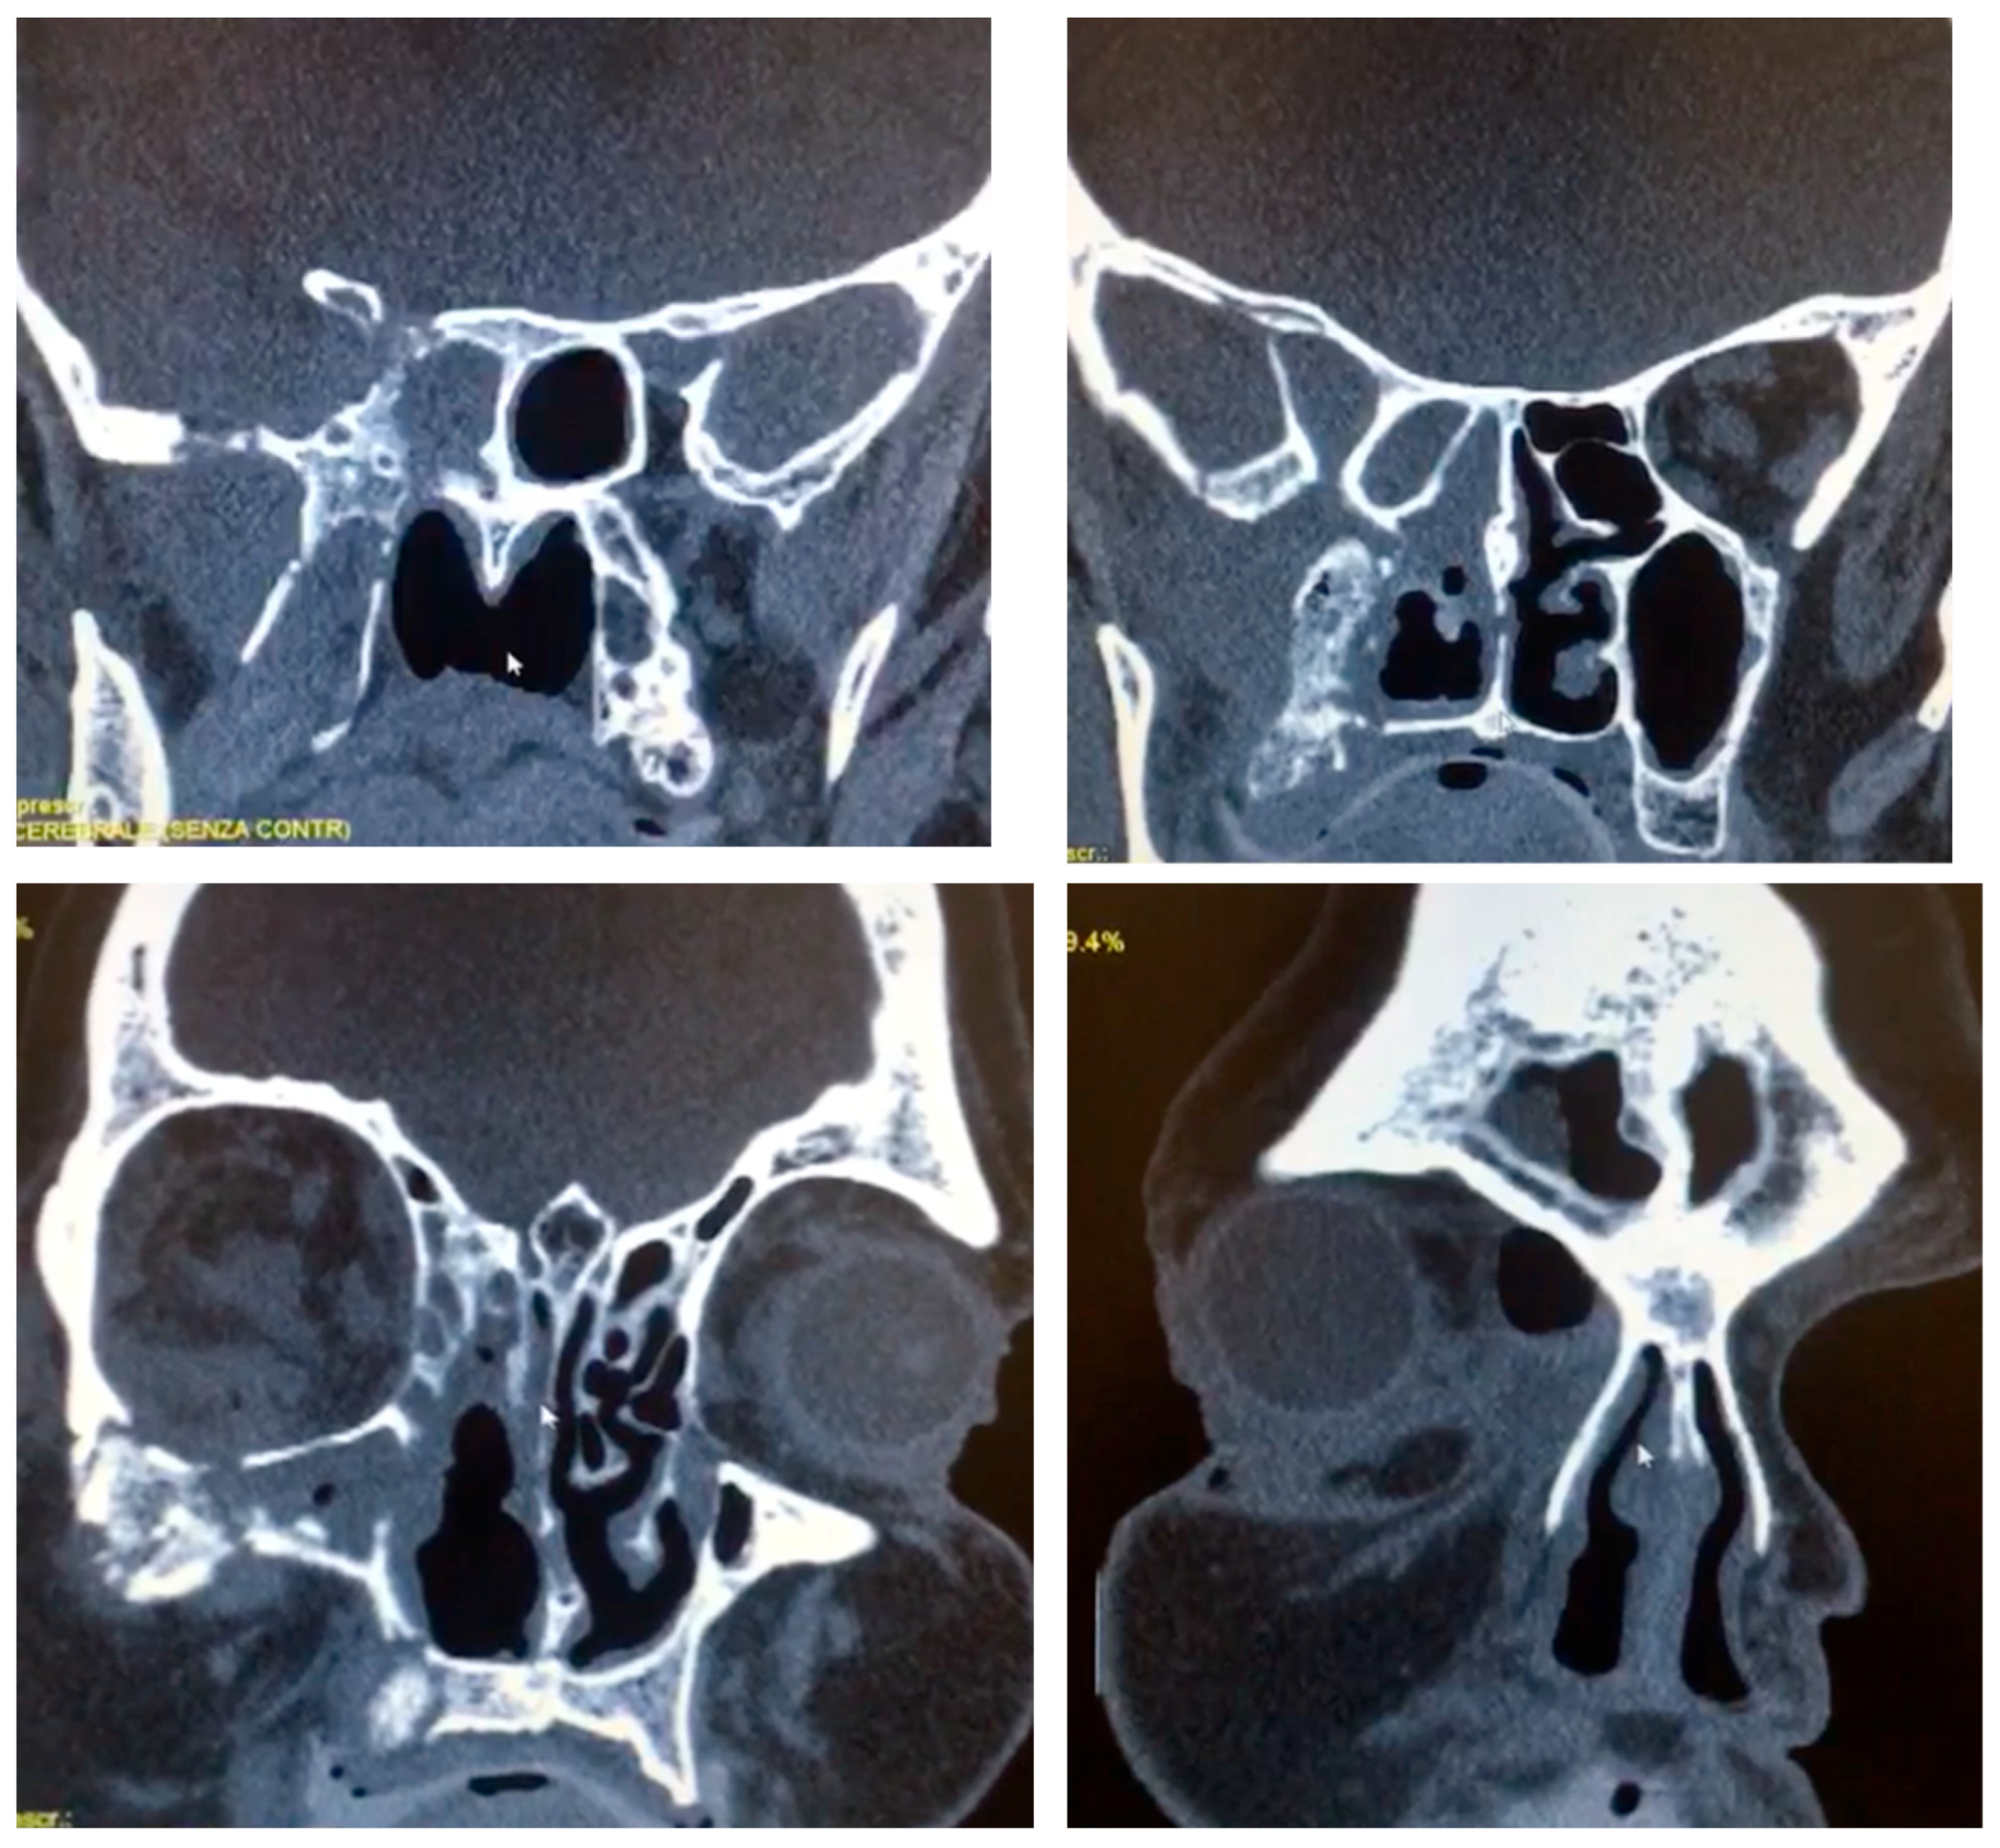

Computed tomography (64-slice MDCT scanner, Siemens Healthineers®, Berlin, Germany) with contrast enhancement, 1.25 mm slice thickness and 262,144 voxels per slice revealed extensive opacification of the right maxillary sinus with associated osteolytic changes involving the maxillary walls, orbital floor, and medial orbital wall (Figure 1). Magnetic resonance imaging (1.5 Tesla MRI, Siemens Healthineers®, Berlin, Germany) demonstrated heterogeneous signal intensity within the affected sinuses with evidence of orbital fat infiltration and extension into the sphenoid sinus with skull base involvement. The imaging findings were highly suggestive of an aggressive infectious process with characteristics consistent with mucormycosis.

Figure 1. CT scan with contrast enhancement showing osteolytic changes involving the right maxillary walls, orbital floor, and medial orbital wall, reaching the sphenoid bone and skull base.